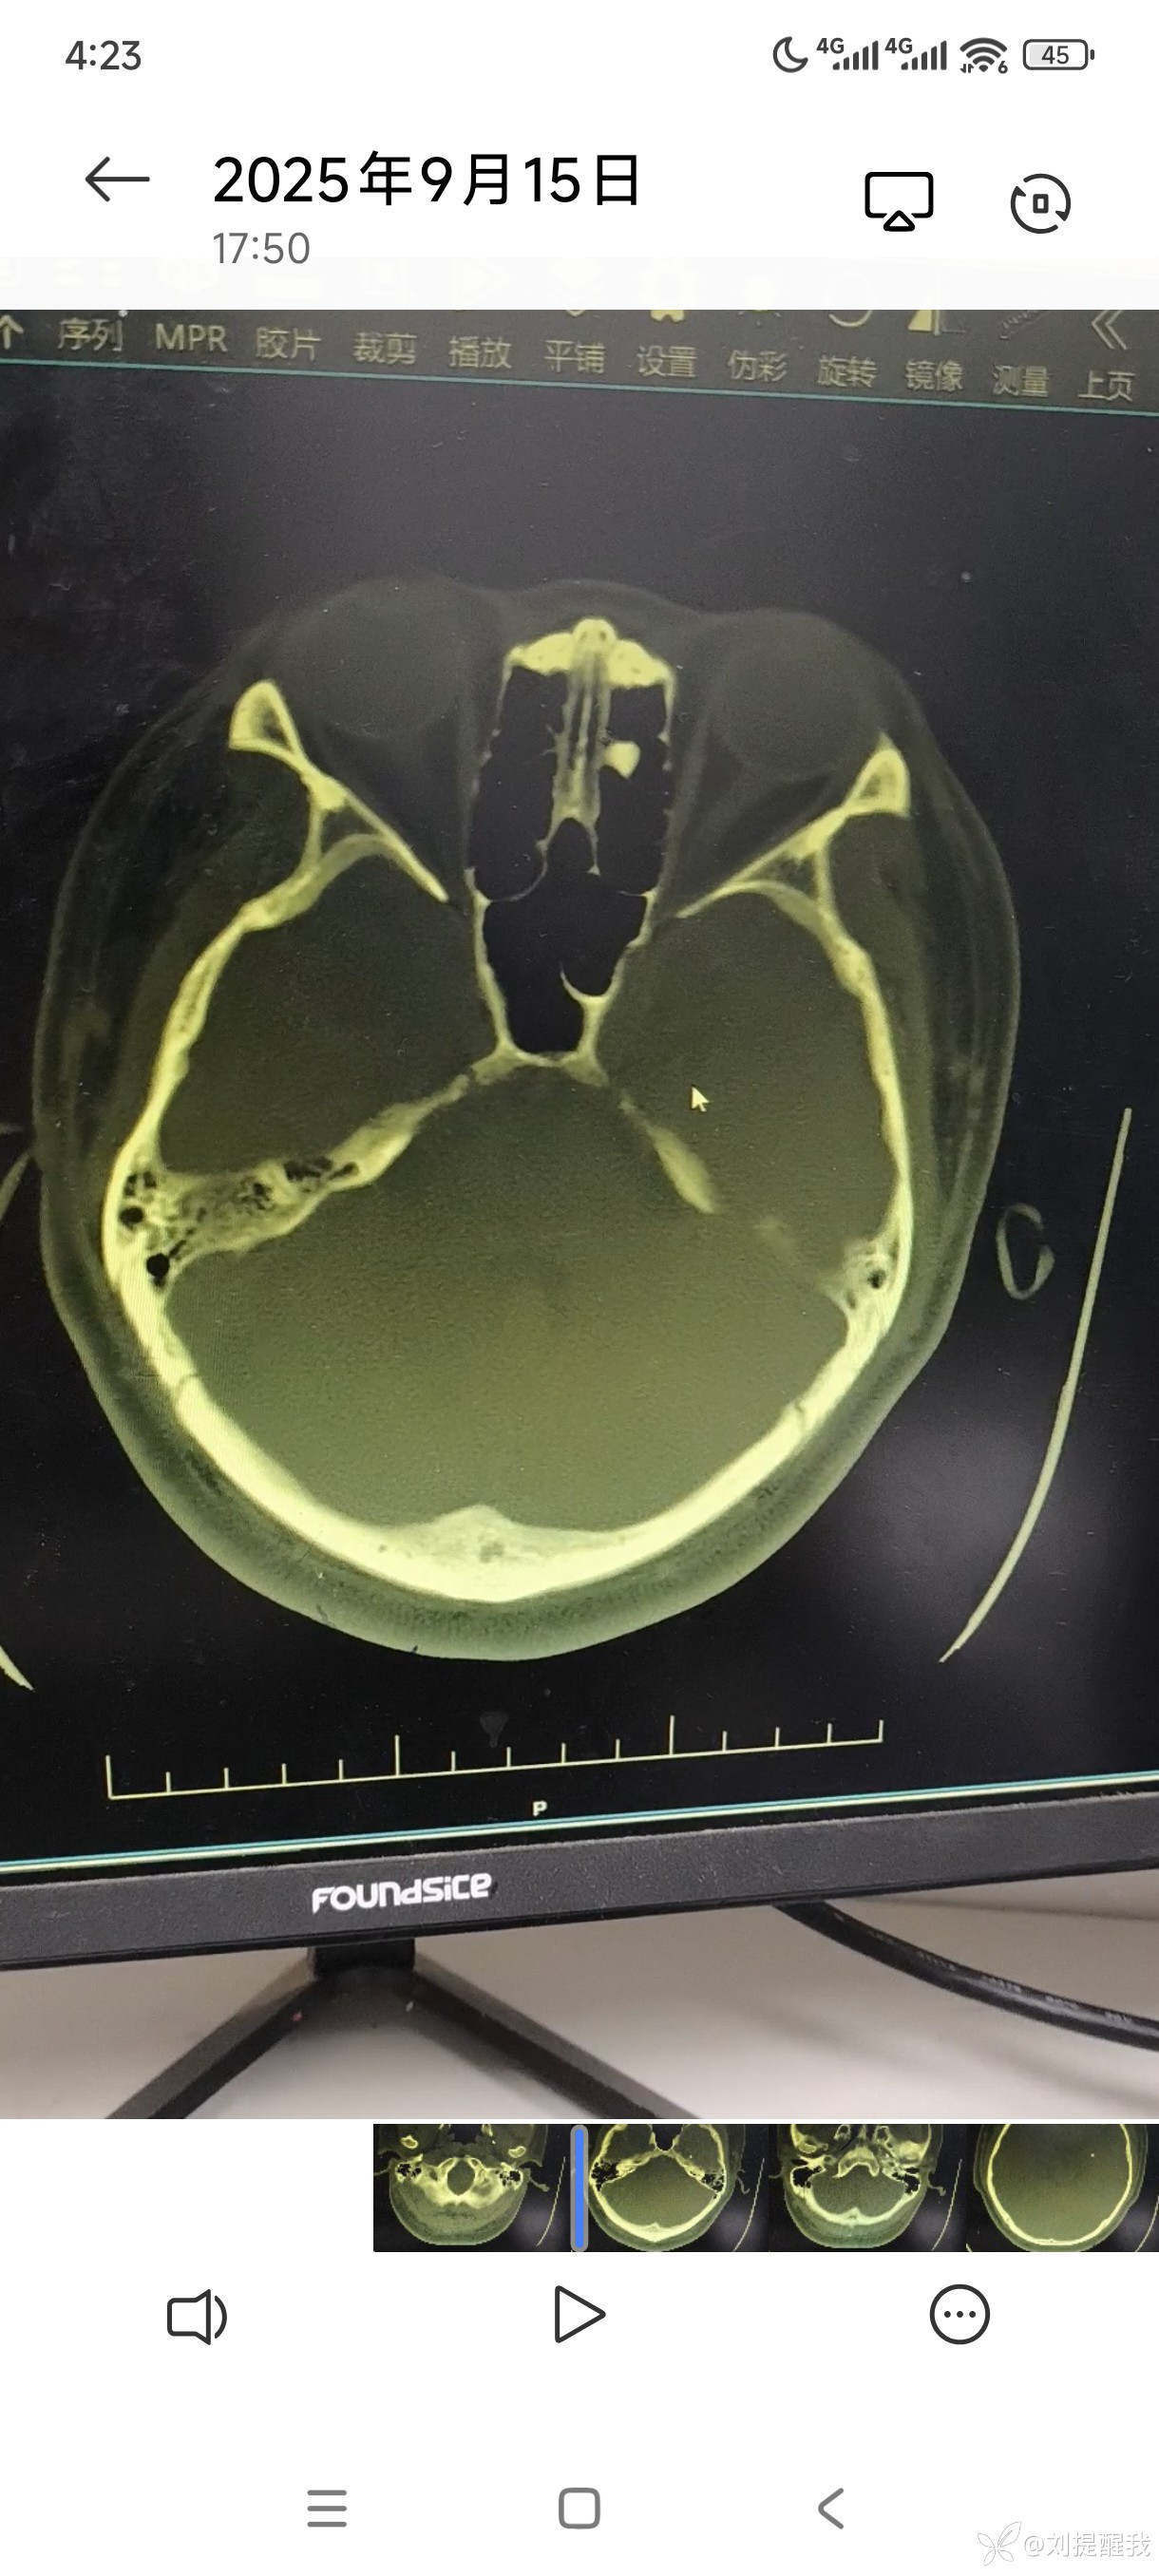

这是鼻窦炎还是异物